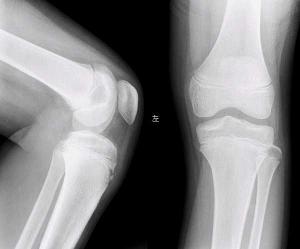

本病又称胫骨结节骨骺炎或骨软骨炎、无菌性坏死、牵引性骨骺炎,是一种少年的疾患,患儿的胫骨结节变大伴疼痛。1903年,Osgood首先报道了一些胫骨结节部分撕脱的病例,不久,Schlatter又提出本病是胫骨上端骨骺的舌状下垂部分的骨骺炎,故本病亦称Osgood-Schlatter病。